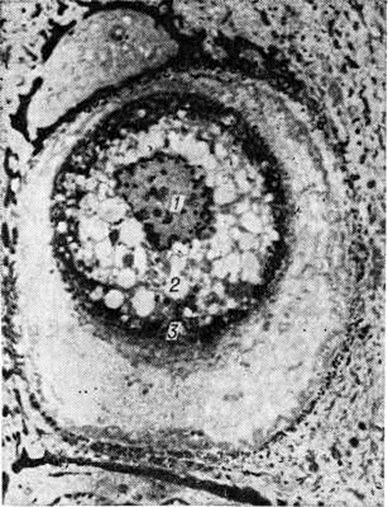

Рис. 2.

Электронограмма круглого тела из эпидермиса при болезни Дарье. Пикнотичное ядро (1) и аутолизированный участок цитоплазмы (2) окружают тонофибриллы (3) в виде грубых пучков. Десмосомы отсутствуют.

В основе Дискератоз лежит нарушение комплекса тонофибриллы — десмосомы, выражающееся в растворении контактного слоя десмосом с последующим отрывом от них тонофибрилл, которые скопляются вокруг ядра. В круглых телах тонофибриллы располагаются вокруг ядра в виде плотных, кератиноподобных пучков, окружающих деструктивно изменённую центральную часть цитоплазмы (рисунок 2). Дальнейшее уплотнение и уменьшение количества кератина в этих клетках с образованием пустых зон приводит к образованию зёрен.